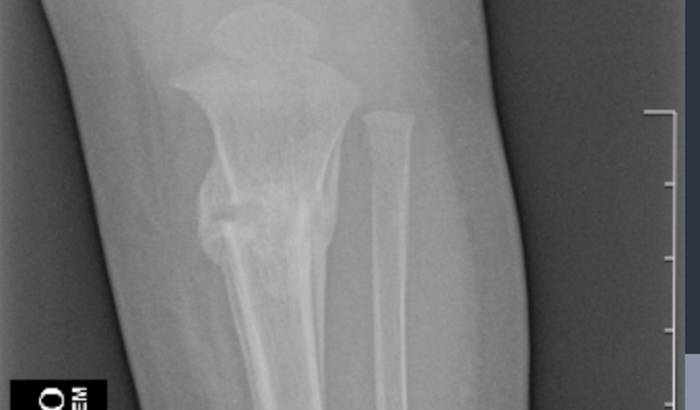

Eu sou Maria Cecília Portilho Pimentel, tenho 9 meses de idade, sofri um acidente de ônibus dia 06-02+2023 o ônibus que bateu na carreta de madeira aqui em Diamantino MT, eu tive traumatismo craniano e uma fratura na perna esquerda, preciso de ajuda para fazer a nova cirurgia para repor o pedaço do crânio na minha cabecinha que está guardado no meu abdome. Mamãe e papai não tem condições de pagar essa cirurgia, e nem as dispensas que vamos ter. Preciso de sua ajuda,,!